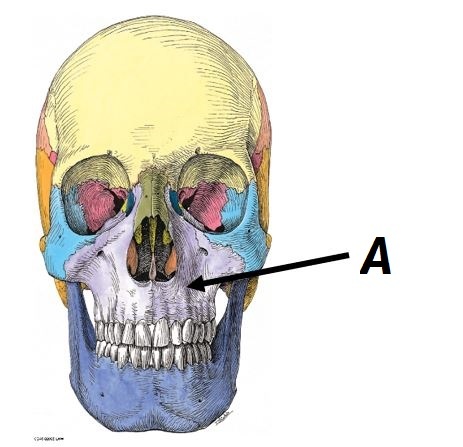

Name bone A

A - Maxilla